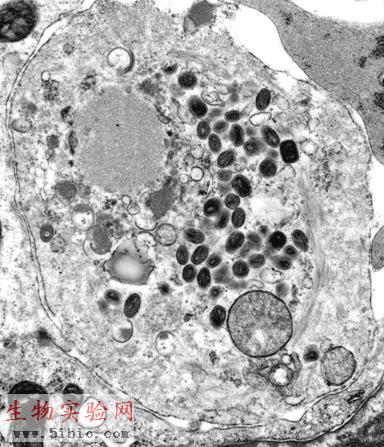

图3-24人类天花病毒(图中深染的颗粒)。图片来自http://www.vetmed.ucdavis.edu